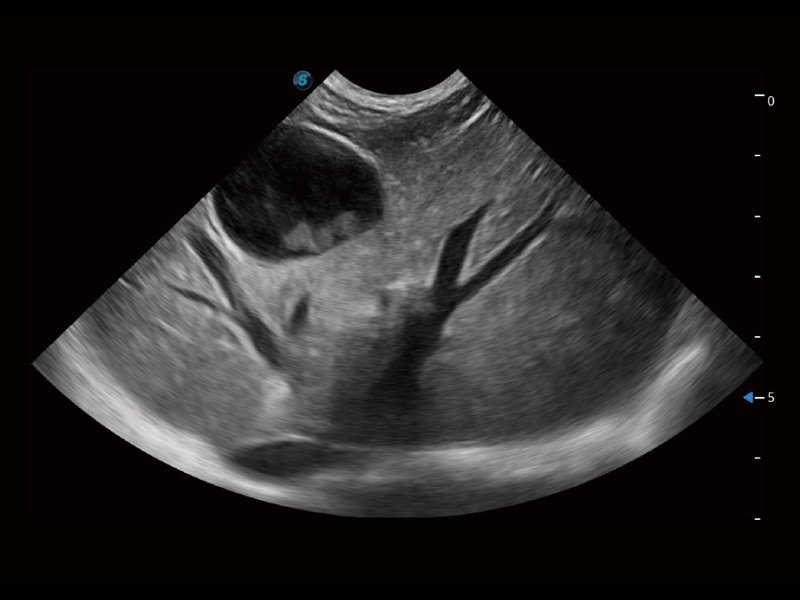

优异的基础图像

ProPet 70 全新的动物超声智能软件和丰富的探头群,为动物医生提供了高清晰度和精细分辨率的图像,无论在宠物、马科、畜牧还是实验室动物等应用中都可以轻松应对,为您的日常工作带来满意的体验。

(犬)肾脏显微血流

(犬)四腔心

(犬)胎儿主动脉弓立体血流

(犬)肝脏

(犬)四腔心MQA